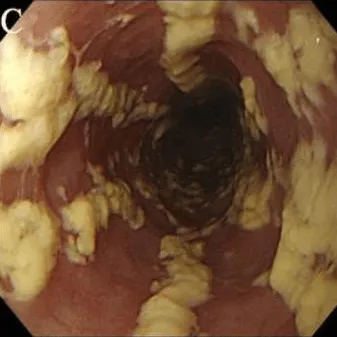

Степень IV

Те же изменения, что и при III степени, плюс контактная кровоточивость слизистой оболочки и иногда сужение просвета пищевода